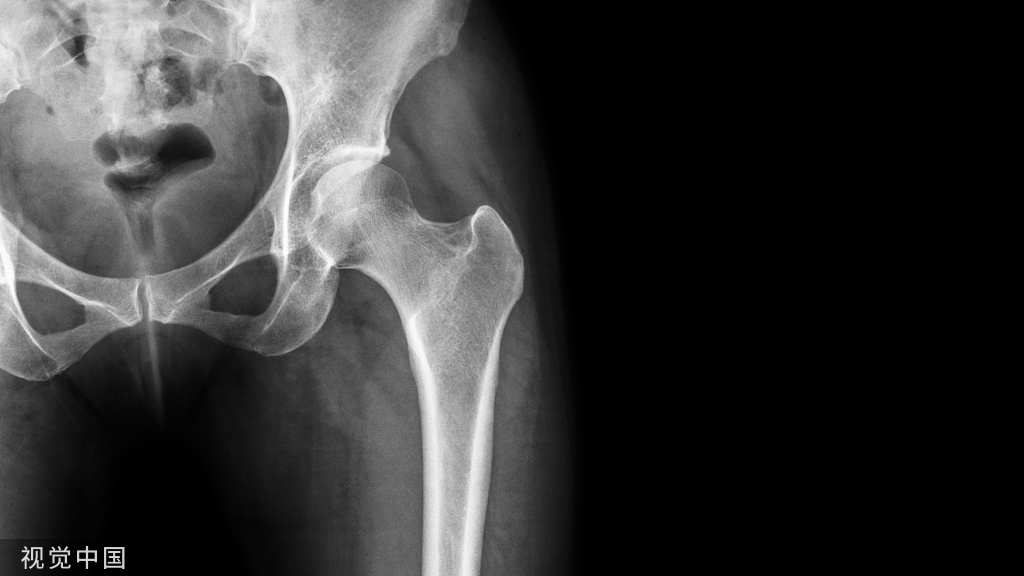

股骨粗隆间骨折(intertrochantericfemoralfracture,IFF),又被称为股骨转子间骨折,是临床最常见的一种髋部骨折。IFF多发于老年患者,流病学统计显示,IFF占髋部骨折36%,占全身骨折的3.51%。